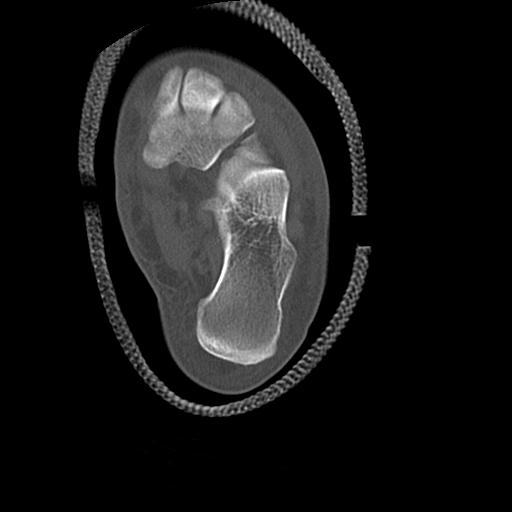

102755 1/4 2R 1/15 2R 右足関節 68歳女性 右三果脱臼骨折